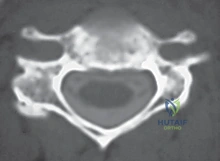

التشريح الدقيق للعمود الفقري العنقي لفهم العملية

لفهم أهمية عملية ACDF، يجب أولاً فهم تشريح الرقبة. يتكون العمود الفقري العنقي من سبع فقرات عظمية (C1 إلى C7). بين كل فقرة وأخرى (باستثناء الأولى والثانية) يوجد "قرص فقري" (Disc) يعمل كوسادة لامتصاص الصدمات وتسهيل حركة الرقبة.

يتكون هذا القرص من جزأين رئيسيين:

1. الحلقة الليفية (Annulus Fibrosus): الغلاف الخارجي القوي والمرن.

2. النواة اللبية (Nucleus Pulposus): مادة هلامية ناعمة في المركز.

خلف هذه الأقراص والفقرات، يمر الحبل الشوكي داخل القناة الشوكية، وتتفرع منه الأعصاب الشوكية التي تخرج عبر فتحات صغيرة (الثقوب الفقرية) لتغذي الكتفين، الذراعين، واليدين. أي خلل في هذا النظام الدقيق يؤدي إلى كارثة عصبية.

- التصوير المقطعي (CT Scan): قد يُطلب للحصول على تفاصيل أدق للتشريح العظمي.